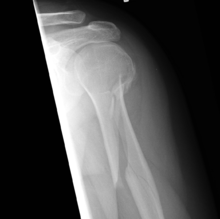

Spiral fracture

A spiral fracture (a.k.a. torsion fracture) is a bone fracture occurring when torque (a rotating force) is applied along the axis of a bone.[1] Spiral fractures often occur when the body is in motion while one extremity is planted. For example, a spiral fracture of the tibia, a bone in the lower leg, can occur in young children when they fall short on an extended leg while jumping. This occurrence is known as "toddler's fracture." Spiral fractures are also recognized as being suspicious in very young children since to obtain a fracture of this sort requires forceful twisting or jerking of the limbs. Child abuse (physical abuse) and certain conditions such as osteogenesis imperfecta (OI) are considered differentials when identifying spiral or torsion fractures.[2]